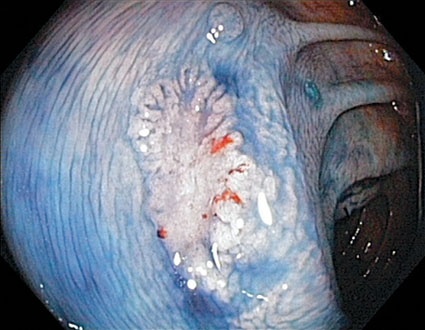

Im Vergleich zur umgebenden Schleimhaut erscheinen sie morphologisch leicht erhaben, vollständig flach oder gering eingesenkt. Während sie in früheren Jahren nur für Japan beschrieben wurden, besteht inzwischen kein Zweifel, dass sie auch in westlichen Ländern vorkommen. Die größte diesbezügliche Studie wurde von amerikanischen Ärzten durchführt, die von japanischen Spezialisten in der Erkennung derartiger Krebsvorstufen bei der Darmspiegelung geschult worden waren. Sie untersuchten über 1.800 Veteranen mittels Koloskopie zur Vorsorge oder zur Abklärung von Beschwerden. 42% der Untersuchten hatten mindestens eine Gewebewucherung. Zumindest eine nicht-polypoide kolorektale Neoplasie wurde bei 9,4% aller Fälle bzw. 5,8% der Vorsorgefälle entdeckt. Polypen wurden etwa fünfmal häufiger nachgewiesen. Allerdings war die Wahrscheinlichkeit schwerer Zellveränderungen oder sogar schon das Vorliegen eines Karzinoms bei den flachen Veränderungen nahezu zehnmal höher als bei den leichter erkennbaren Polypen.

Die gute Nachricht ist, dass die nicht-polypoiden Krebsvorstufen mit den heutigen Techniken der Koloskopie entdeckt und auch häufig in derselben Sitzung entfernt werden können. Die wichtigsten diagnostischen Voraussetzungen sind eine entsprechende Erfahrung des Untersuchers, eine gute Darmreinigung, eine ausreichend lange Untersuchungszeit sowie der Einsatz moderner hochauflösender Endoskope, gegebenenfalls mit Einsatz elektronischer oder konventioneller Chromoendoskopie. Die Abtragung derartiger Veränderungen erfordert spezielle Techniken wie die der endoskopischen Mukosaresektion (EMR) oder Submukosadissektion (ESD). Die Entfernung großflächiger nicht-polypoider kolorektaler Neoplasien erfolgt vorwiegend unter stationären Bedingungen in Zentren, insbesondere aufgrund des erhöhten Komplikationsrisikos.